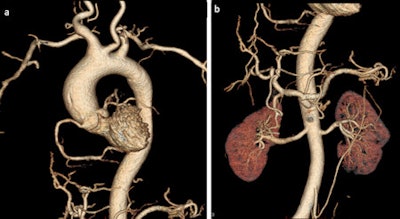

Coronary calcifications and stenoses are shown in 2D and 3D images in two cases of sudden cardiac death due to coronary artery disease.One solution for implementing PMCTA into the daily routine of legal medicine is the introduction of radiographers to help with the additional examination. In fact, the forensic radiographer has become a new subspecialty in some countries, and international training is available, they noted.